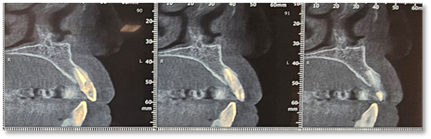

Radiological examination (Figure 2) showed no periapical infection or desmodontal enlargement, and the presence of a thin layer of vestibular bone, so tooth 22 was deemed irrecoverable.

Figure 2: Sagittal sections of the CBCT of the patient.